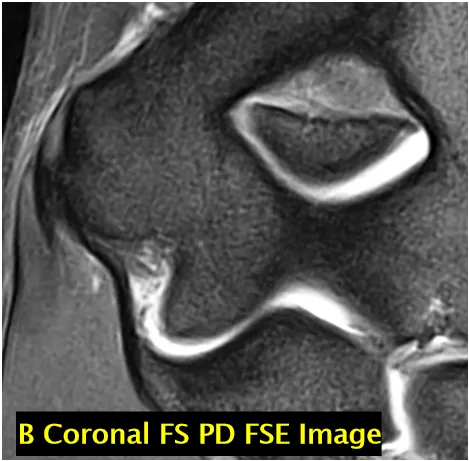

正常变异与诊断陷阱(一)

• 滑车沟假缺损(A 图):不应与骨软骨缺损混淆(箭头标注);成像序列:矢状面 T2 加权快速自旋回波图像;

• 横行滑车嵴(B 图):不应与中央骨赘混淆(箭头标注);成像序列:矢状面 T1 加权快速自旋回波图像;

• 肱骨小头假缺损(C 图):肱骨小头后下侧的正常裸露区(箭头标注),不应与骨软骨损伤混淆;成像序列:矢状面脂肪抑制 T2 加权快速自旋回波图像;

• 3 幅对应 MRI 图像(标注 A-C)